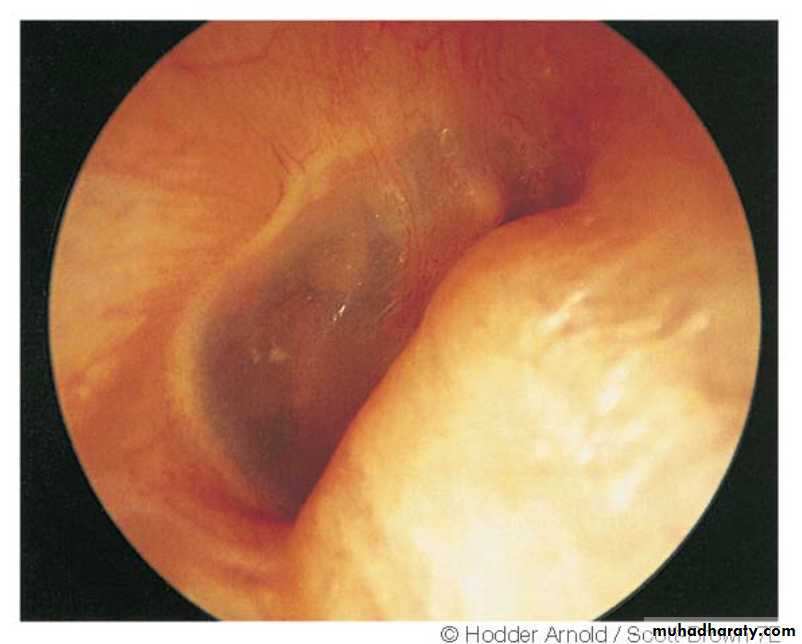

Otoscopy

"Rising sun" appearance is seen when tumour arises from the floor of middle ear.